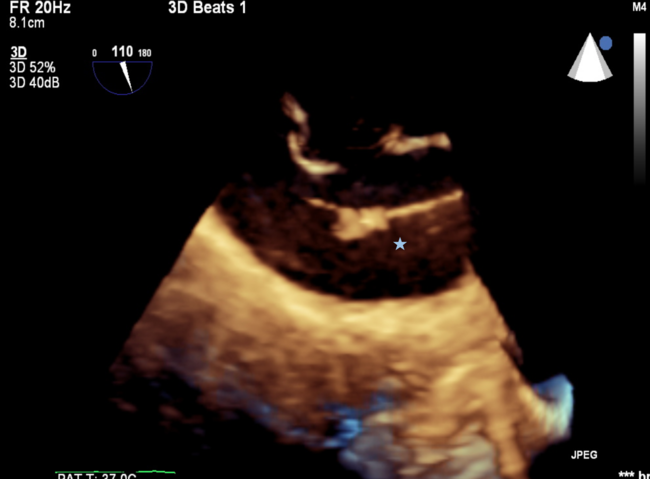

At the beginning of the procedure, the patient received unfractionated heparin and achieved an appropriate activated clotting time of 220 seconds. During right heart catheterization, the patient developed acute onset atrial fibrillation. As the catheter was advanced through the ASD, thrombotic material was suspected on 2-dimensional transesophageal echocardiography (TEE). Three-dimensional TEE confirmed the presence of a large thrombus attached to the Eustachian valve (Figure, Videos 1-3).